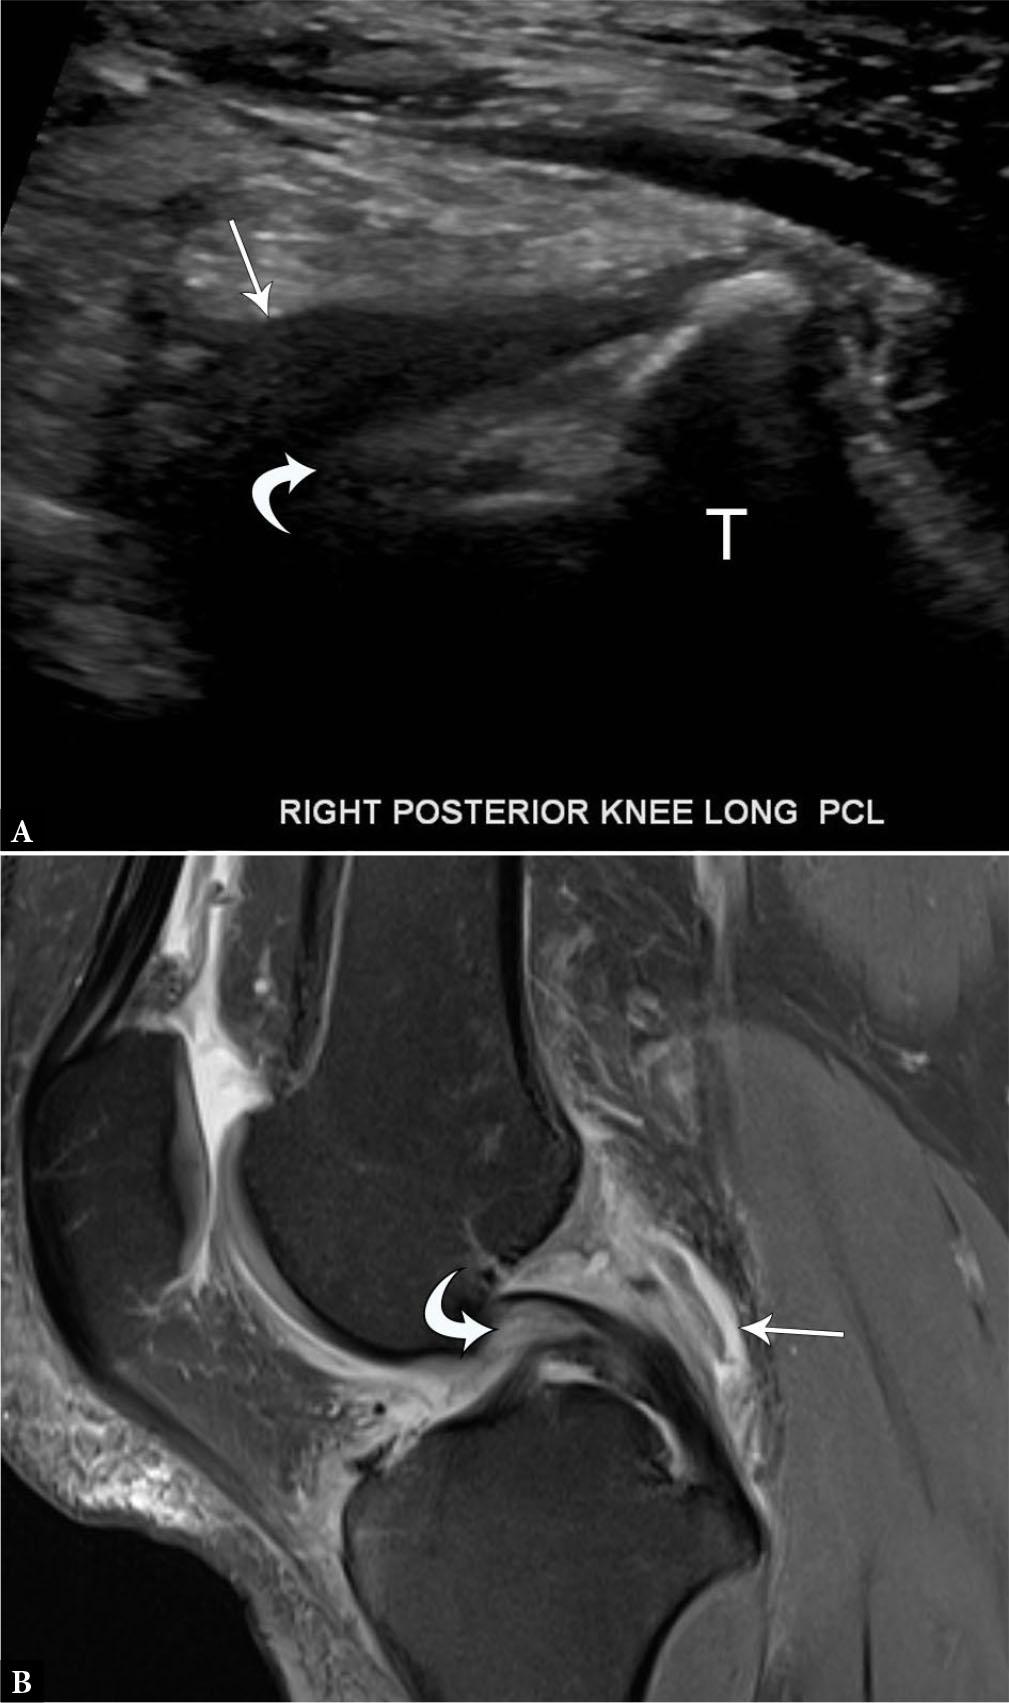

Fig. 6.

33-year-old male with partial posterior cruciate ligament tear. A. Longitudinal grayscale US image of the PCL demonstrates normal tibial attachment but indistinct, hypoechoic proximal fibers (curved arrow) with surrounding hypoechoic material (arrow). B. Sagittal proton-density-weighted fat-suppressed MR image shows edema and thickening of the proximal PCL (curved arrow) with surrounding edema and fluid (arrow)